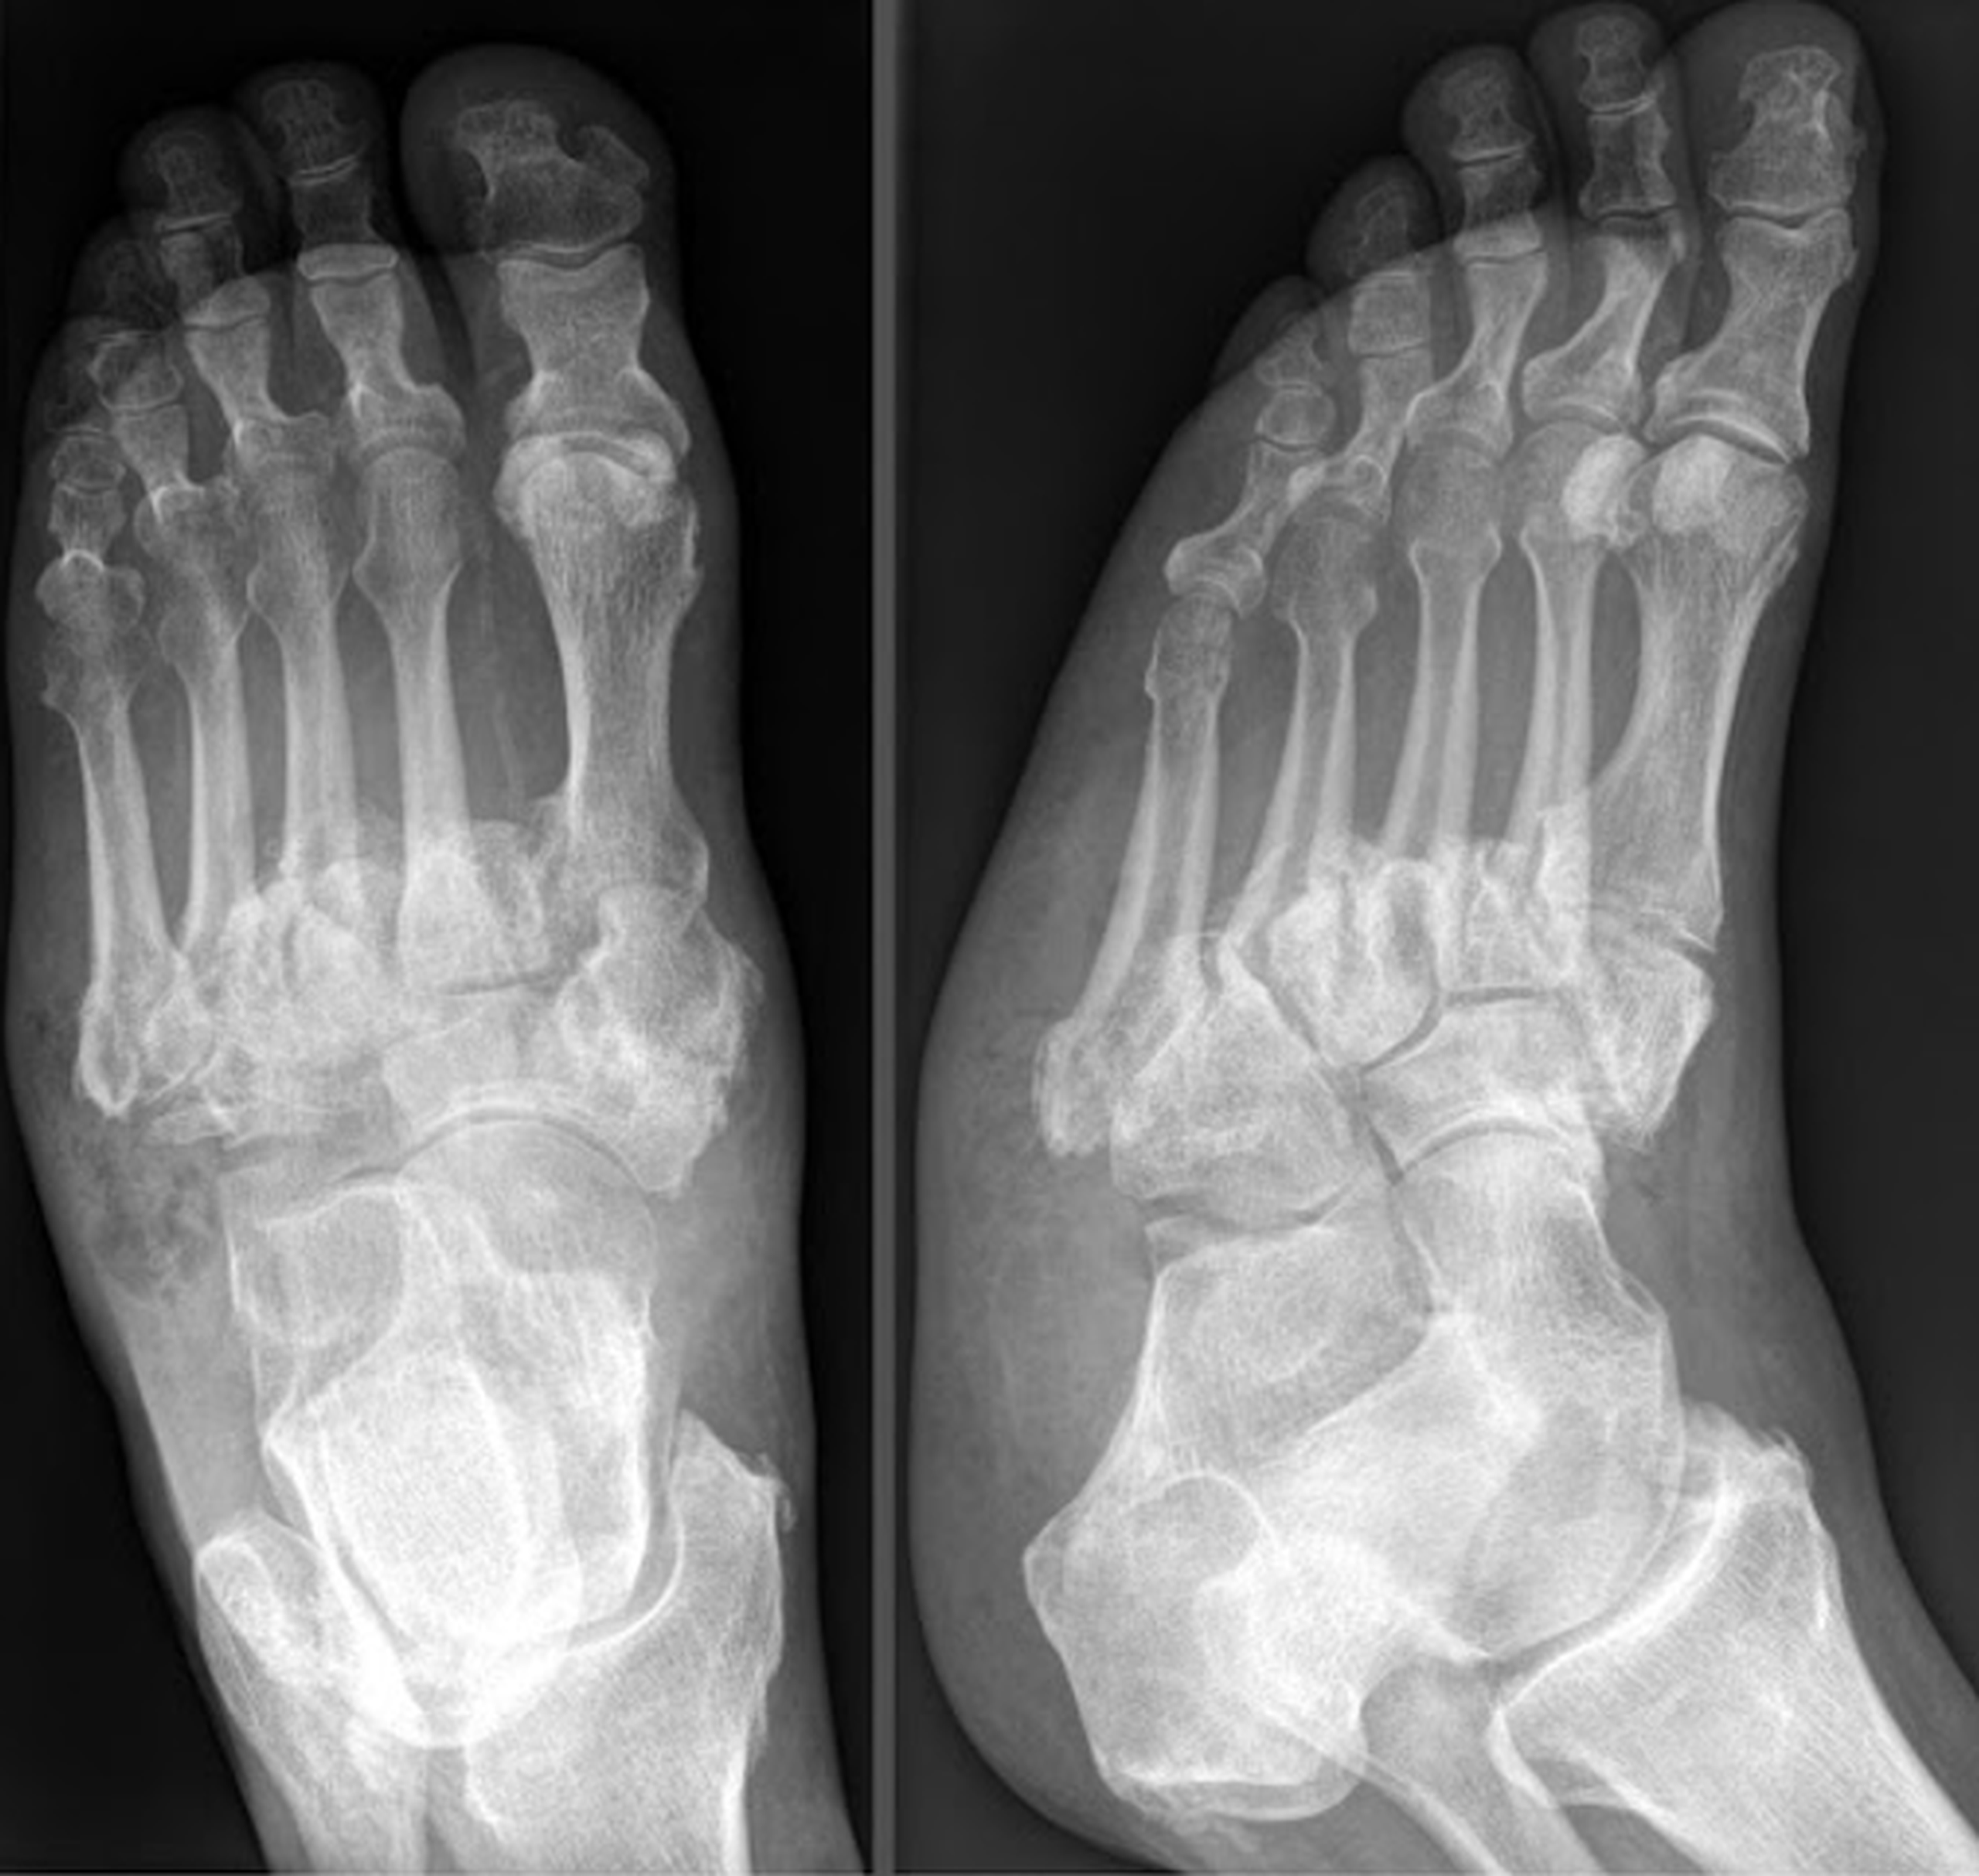

Bệnh khớp do thần kinh (hay còn gọi là bệnh Charcot) là những thay đổi về xương và khớp xảy ra thứ phát do mất cảm giác và thường liên quan nhất đến bệnh đái tháo đường, giang mai, sa xương sống, nứt đốt sống, chấn thương tủy sống và bệnh phong. Những thay đổi trên X-quang của bệnh lý này bao gồm phá hủy bề mặt khớp, xương dưới sụn mờ đục, mảnh vỡ khớp, biến dạng và trật khớp.

Mặc dù nhiều khớp có thể bị ảnh hưởng, nhưng thường gặp nhất ở đầu gối và mắt cá chân thường. Sự phân bố phụ thuộc phần lớn vào bệnh căn nguyên, như: Giang mai gây biến chứng thần kinh (tabes dorsalis) ảnh hưởng đến đầu gối và hông, và bệnh đái tháo đường ảnh hưởng đến bàn chân và mắt cá chân. Bệnh rỗng tủy xương (Syringomyelia) thường ảnh hưởng đến cột sống và các khớp chi trên, đặc biệt là khuỷu tay và vai. Thông thường, chỉ có một khớp bị ảnh hưởng và không quá hai hoặc ba (ngoại trừ các khớp nhỏ của bàn chân), phân bố không đối xứng.